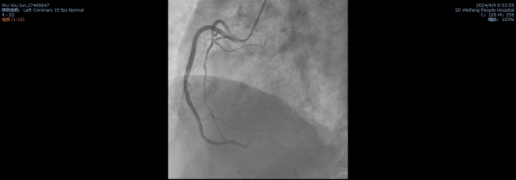

患者的一系列结果与症状都指向急性心肌梗死,立即在北辰院区行冠状动脉造影术,冠脉造影结果: